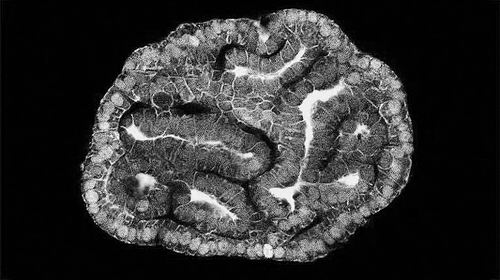

由羊膜细胞制成的肾类器官。图片来源:Giuseppe Calà

为了探索这些细胞是否可用于产生类器官,作者培养了这些细胞,观察到它们开始增殖并自组织成三维类器官,在两周内可见。研究人员发现,这些细胞会形成组织特异性原生胎儿类器官,即小肠、肾脏和肺,并显示出来源组织的功能性特征。目前,作者能够利用这一技术,从患先天性膈疝的胎儿的羊水和气管液细胞中,培育出再现这种疾病某些特征的肺类器官。